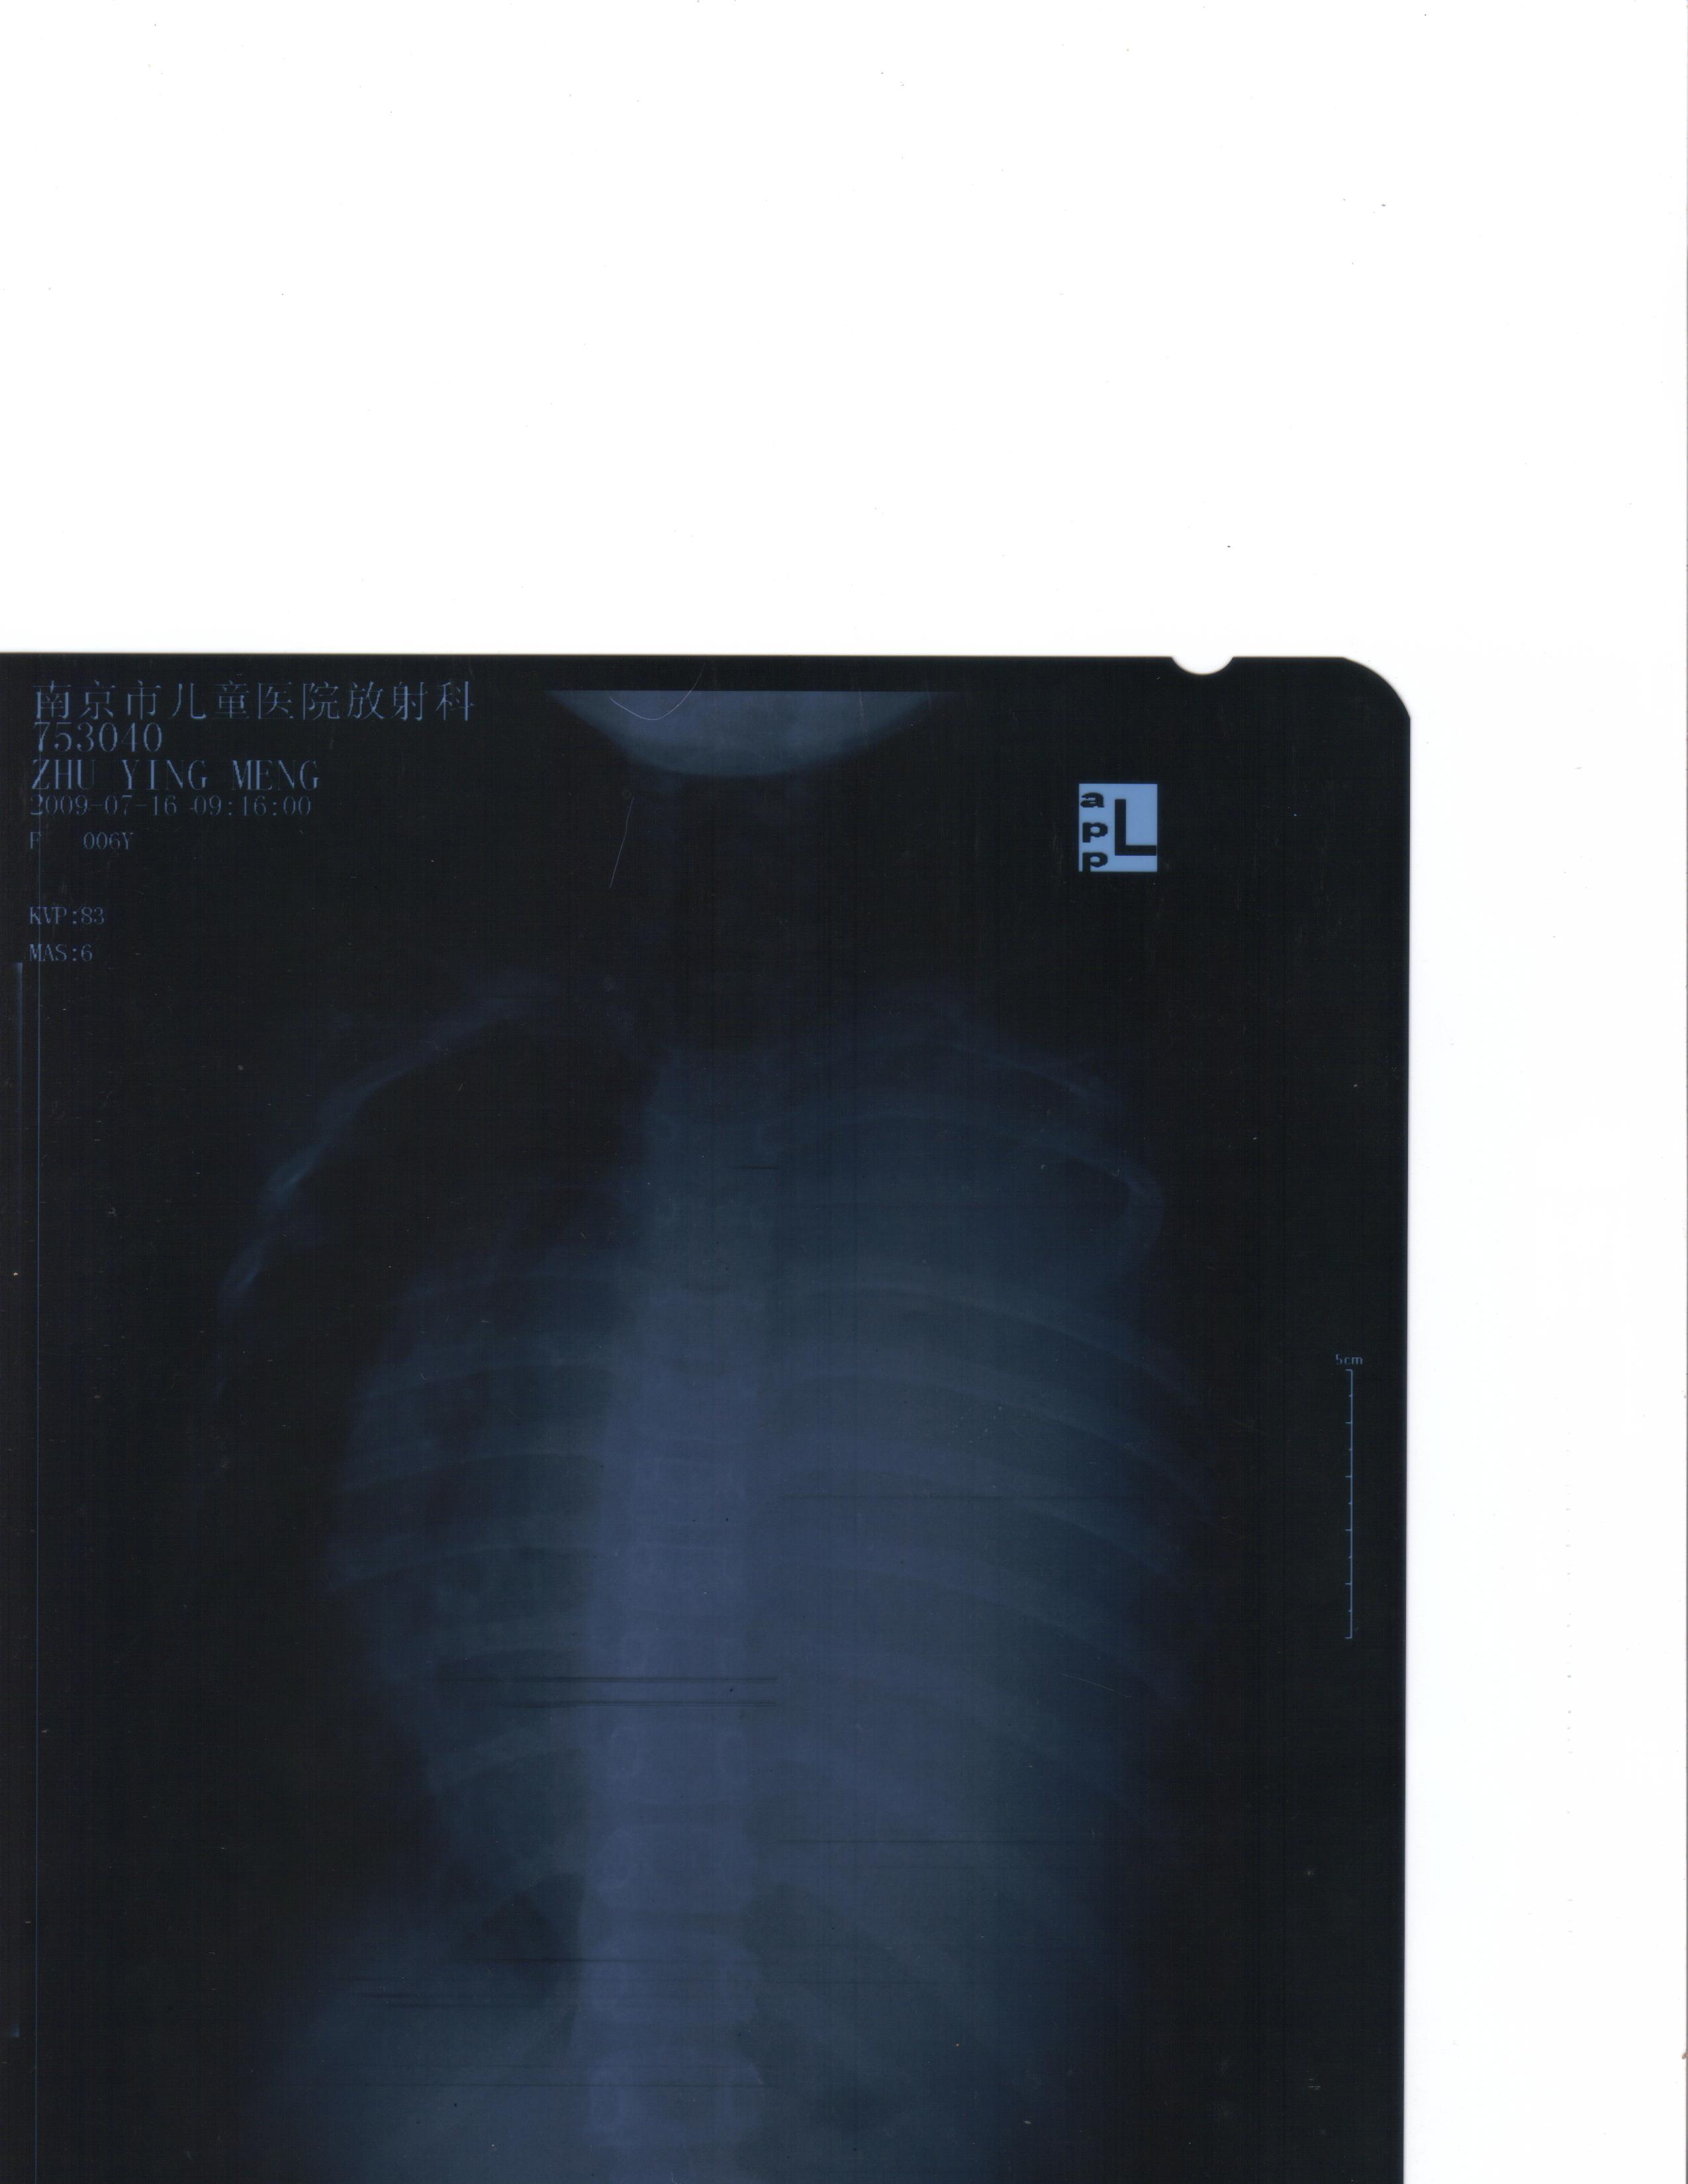

• 有对胸腔畸胎瘤比较擅长的高人吗? attachment

• 准确的说是我的一个外甥女,她今年七岁,平常比较消瘦。父母总以为是她挑食的原故而没有太多的在意。 今年前段时间因为天气比较热,小孩总说呼吸难受,胸闷。所以家人就带她去医院检查,一拍片连医生都吓了一跳, ...  阅读全文>